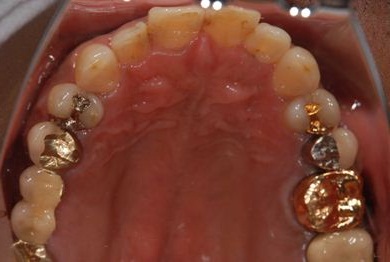

インプラントの症例写真 IMPLANT

インプラント治療+セラミック治療

| 治療内容 | インプラント2本、メタルボンドセラミッククラウン7本(メタルボンド用土台5本)、歯肉歯槽骨整形手術 | ||||||||||||||||||||||||||||||||